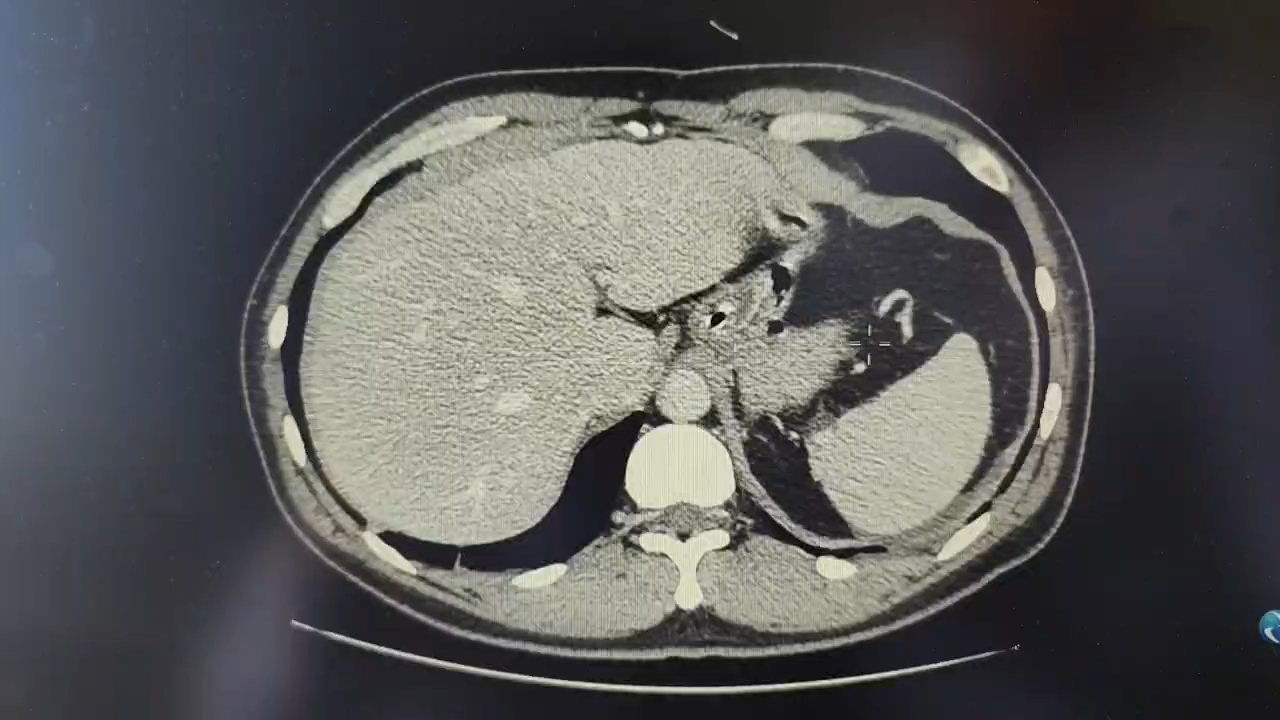

患者急诊CT显示肠管扩张,积气积液。急性机械性小肠梗阻诊断明确。禁食输液、胃肠减压保守治疗,2天梗阻持续无缓解,腹部绞痛加剧,左侧腹部压痛显著。腹部CT复查肠梗阻加重,并见左侧中腹部的“漩涡征”,提示肠扭转。遂急诊剖腹探查,中上腹正中绕脐切口。发现上腹腹腔间隙存在,充斥梗阻近端扩张的肠襻,色泽稍深,血运大致正常。自脐周中腹以下肠襻与腹壁、肠襻相互间弥漫性粘连,形成多处粘连索带和肠襻卡压点。未见肠襻扭转,腹腔少量淡黄色渗液。粘连松解过程顺利,无肠管损伤。解除梗阻,顺直肠管及系膜,直至左下腹盆腔的吻合口。放置腹腔引流管后结束手术。术后3天,肛门排便排气,无腹胀腹痛。观察2天后,拔除胃管和腹腔引流管,允许少量饮水,仍禁食。术后第八天感腹胀,肛门无排气。胃肠减压有多量绿色胃液。CT复查见肠管扩张,积气积液。考虑炎性肠梗阻,继续禁食禁饮胃肠减压,静脉营养支持治疗。

急诊入院腹部CT: